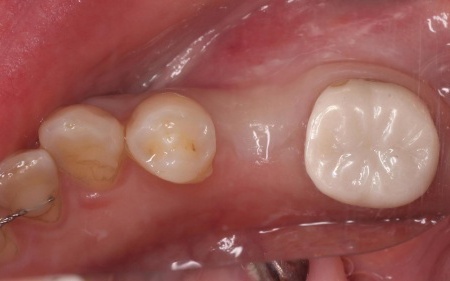

| 行ったご提案・治療内容 | 診断結果をお伝えし、患者様の了承を得たうえで左下奥歯の被せ物を外したところ、レントゲン検査での診断どおり、歯根が割れていることが確認できました。 そのため、患者様には左上下奥歯とも温存が難しい旨を説明し、抜歯に同意いただきました。 患者様は、以前当院で人工歯根を顎の骨に埋入して歯を装着するインプラント治療を受けていたため、今回も左上下奥歯ともインプラント治療を希望されています。 メリット デメリット 改めてメリットとデメリットをしっかりお伝えしたところ、インプラント治療に対する不安はないとのことで、治療に同意いただきました。 まず、左上下奥歯を慎重に抜きます。 インプラント手術後は経過観察を行い、インプラントが顎の骨に結合したことを確認したら、インプラント上部に取り付ける人工歯を作製するために精密な型取りを実施します。 後日、完成した人工歯をインプラントに装着し、使用感や見た目に問題がないことを確認して、治療を終了しました。 |

治療後